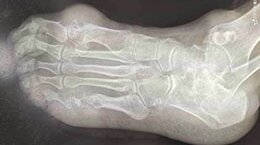

由于尿酸盐沉积在关节囊、滑囊、软骨、骨质和其他组织中而引起病损及炎性反应,其多有遗传因素,好发于40岁以上男性,多见于第一跖趾关节,也可发生于其他较大关节,尤其是踝部与足部关节。